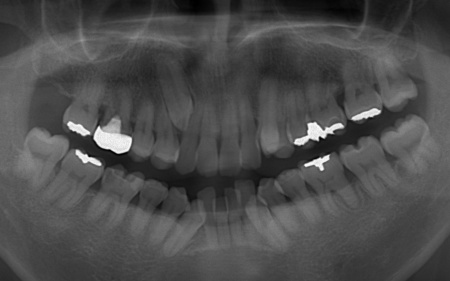

またレントゲン撮影をして確認すると、右上前歯は顎の骨の中に埋まっている骨性埋伏(こっせいまいふく)の状態でした。

さらに、左下奥歯は重度の歯周病であり、歯を支えている骨が一部溶けていることが判明しました。

このまま放置すると骨がさらに溶け、歯を残すことが難しくなるおそれがあります。

今回のケースでは、左上下の奥歯各1本(第3大臼歯)、右下の奥歯1本(第3大臼歯)、左上下と右下の奥歯各1本(第1小臼歯)の計6本の抜歯が必要です。

骨に埋まっている右上前歯は引っ張り出すことができないため、隣の歯である右上奥歯(第1小臼歯)を代用歯として機能させる方法を選択しました。

②矯正治療後、歯周病を発症している左下奥歯(第1大臼歯)を温存するために、失われた骨や歯茎を再生する「歯周再生療法」を行う